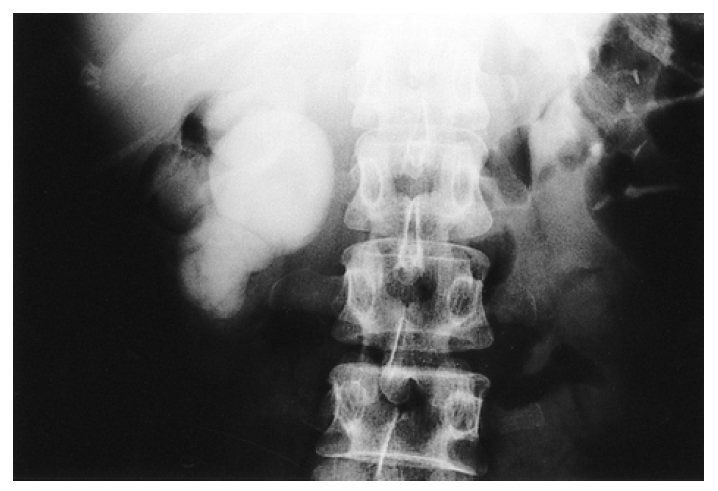

Kidney ultrasonogram showed a marked dilatation of the right pelvocalyceal system and right proximal ureter. However, the left kidney showed normal appearance. Excretory urogram revealed a marked right hydronephrosis with dilated calyces due to ureteropelvic junction obstruction (Figure 1). Computed tomography angiogram (CTA) clearly displayed the aberrant renal artery which originated from the aorta below the normal right renal artery (Figure 2). A source image of magnetic resonance angiogram (MRA) also showed a severe hydronephrosis of the right kidney and smooth obstruction of the right ureteropelvic junction due to extrinsic compression by an aberrant renal artery which originated from the aorta, crossing anteriorly to the ureteropelvic junction (Figure 3). Retrograde pyelogram demonstrated linear indentation of the proximal ureter (Figure 4). Tc-99m DTPA renal scan revealed a markedly delayed excretion of the right kidney. After furosemide infusion, the delayed right kidney excretion was somewhat improved (Figure 5).

Figure 4.

Retrograde pyelogram demonstrates extrinsic indentation (arrow) at the right ureteropelvic junction with severe hydronephrosis.